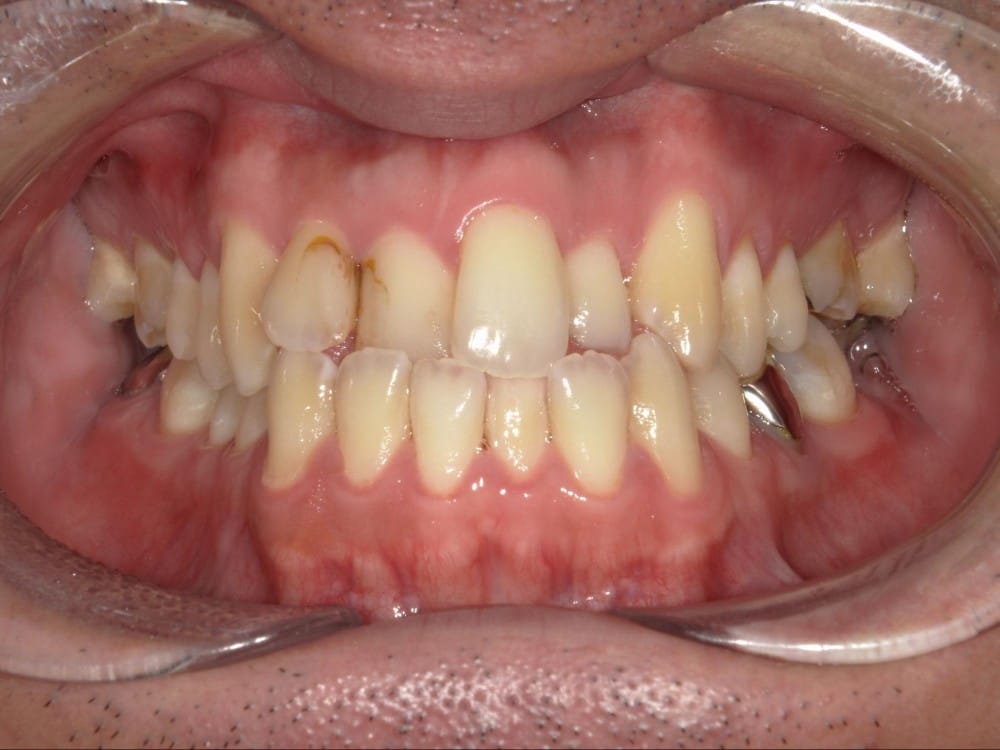

30代の男性で、受け口とガタガタを主訴にご来院されました。

治療前の様子

分析しますと

- 骨格的な上下あごの前後差は重度

- 噛み合わせの位置も下あごの奥歯が半分くらい前にズレていた

- 上の前歯が前に傾斜、下の前歯が内側に傾斜しているにもかかわらず、受け口

というケースで、外科的な処置も検討するようなケースでした。

骨格的なズレや奥歯の噛み合わせのズレもあり、重度の受け口でしたが、なんとか歯列矯正のみで受け口を改善できると診断し、治療を開始しました。

先ほどの2ケースと同じように、患者さまに外科的な手術の選択肢も提示しましたが、希望されず、横顔の変化はおそらく起こらないことを納得の上、治療をスタートいたしました。

今回のケースも奥歯の移動量が大きいため、マウスピースだけでは難しいと判断し、カリエールとよばれる装置を補助的に使用し、上下の噛み合わせの前後関係を整えることで、手術を行わずに機能面と見た目の両方が改善することにしました。

治療後の写真です。

<治療前後の比較です>

正面から見た時の受け口は改善していますが、横顔の変化は軽微かほとんど起こっていません。

同じように治したケースでも横顔の変化には差があります。

だからこそ、治療前に「どこまでを目標にするのか」をしっかり共有し、噛み合わせ改善を軸に治療を進めることが大切になります。